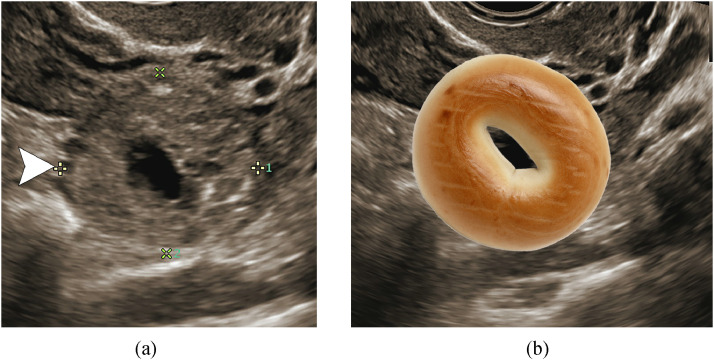

The correlation of a ring-like adnexal structure on ultrasonography (Fig. 2a) to a tubal ectopic pregnancy dates back to at least 1978 [1]. The first description of this ring-like structure as a “bagel” appears to have occurred in 1995 during a personal communication between Drs. S. Goldstein and S. Rottem [2]. Sonographically, the centrally hypoechoic hole of the bagel represents the gestational sac and the thick surrounding echogenic dough of the bagel represents the trophoblastic tissue (Fig. 2b). A fetal pole would not be present as this would be confirmatory of an ectopic pregnancy.

Fig. 2.

The “bagel sign.” A 32-year-old pregnant patient (6 weeks gestational age based on last menstrual period) re-presented with pelvic pain and vaginal bleeding. Beta-hCG measured 1657 mIU/mL compared to 225 mIU/mL 3 days prior. (a) Grayscale pelvic ultrasound of the left adnexa demonstrates a ring-like structure with a thick, solid, hyperechoic periphery and fluid centrally: the “bagel sign” (arrowhead) (calipers along the periphery were placed to measure the size of the structure). (b) Bagel animation overlaid on top of the sonographic finding. Ectopic pregnancy was confirmed clinically.